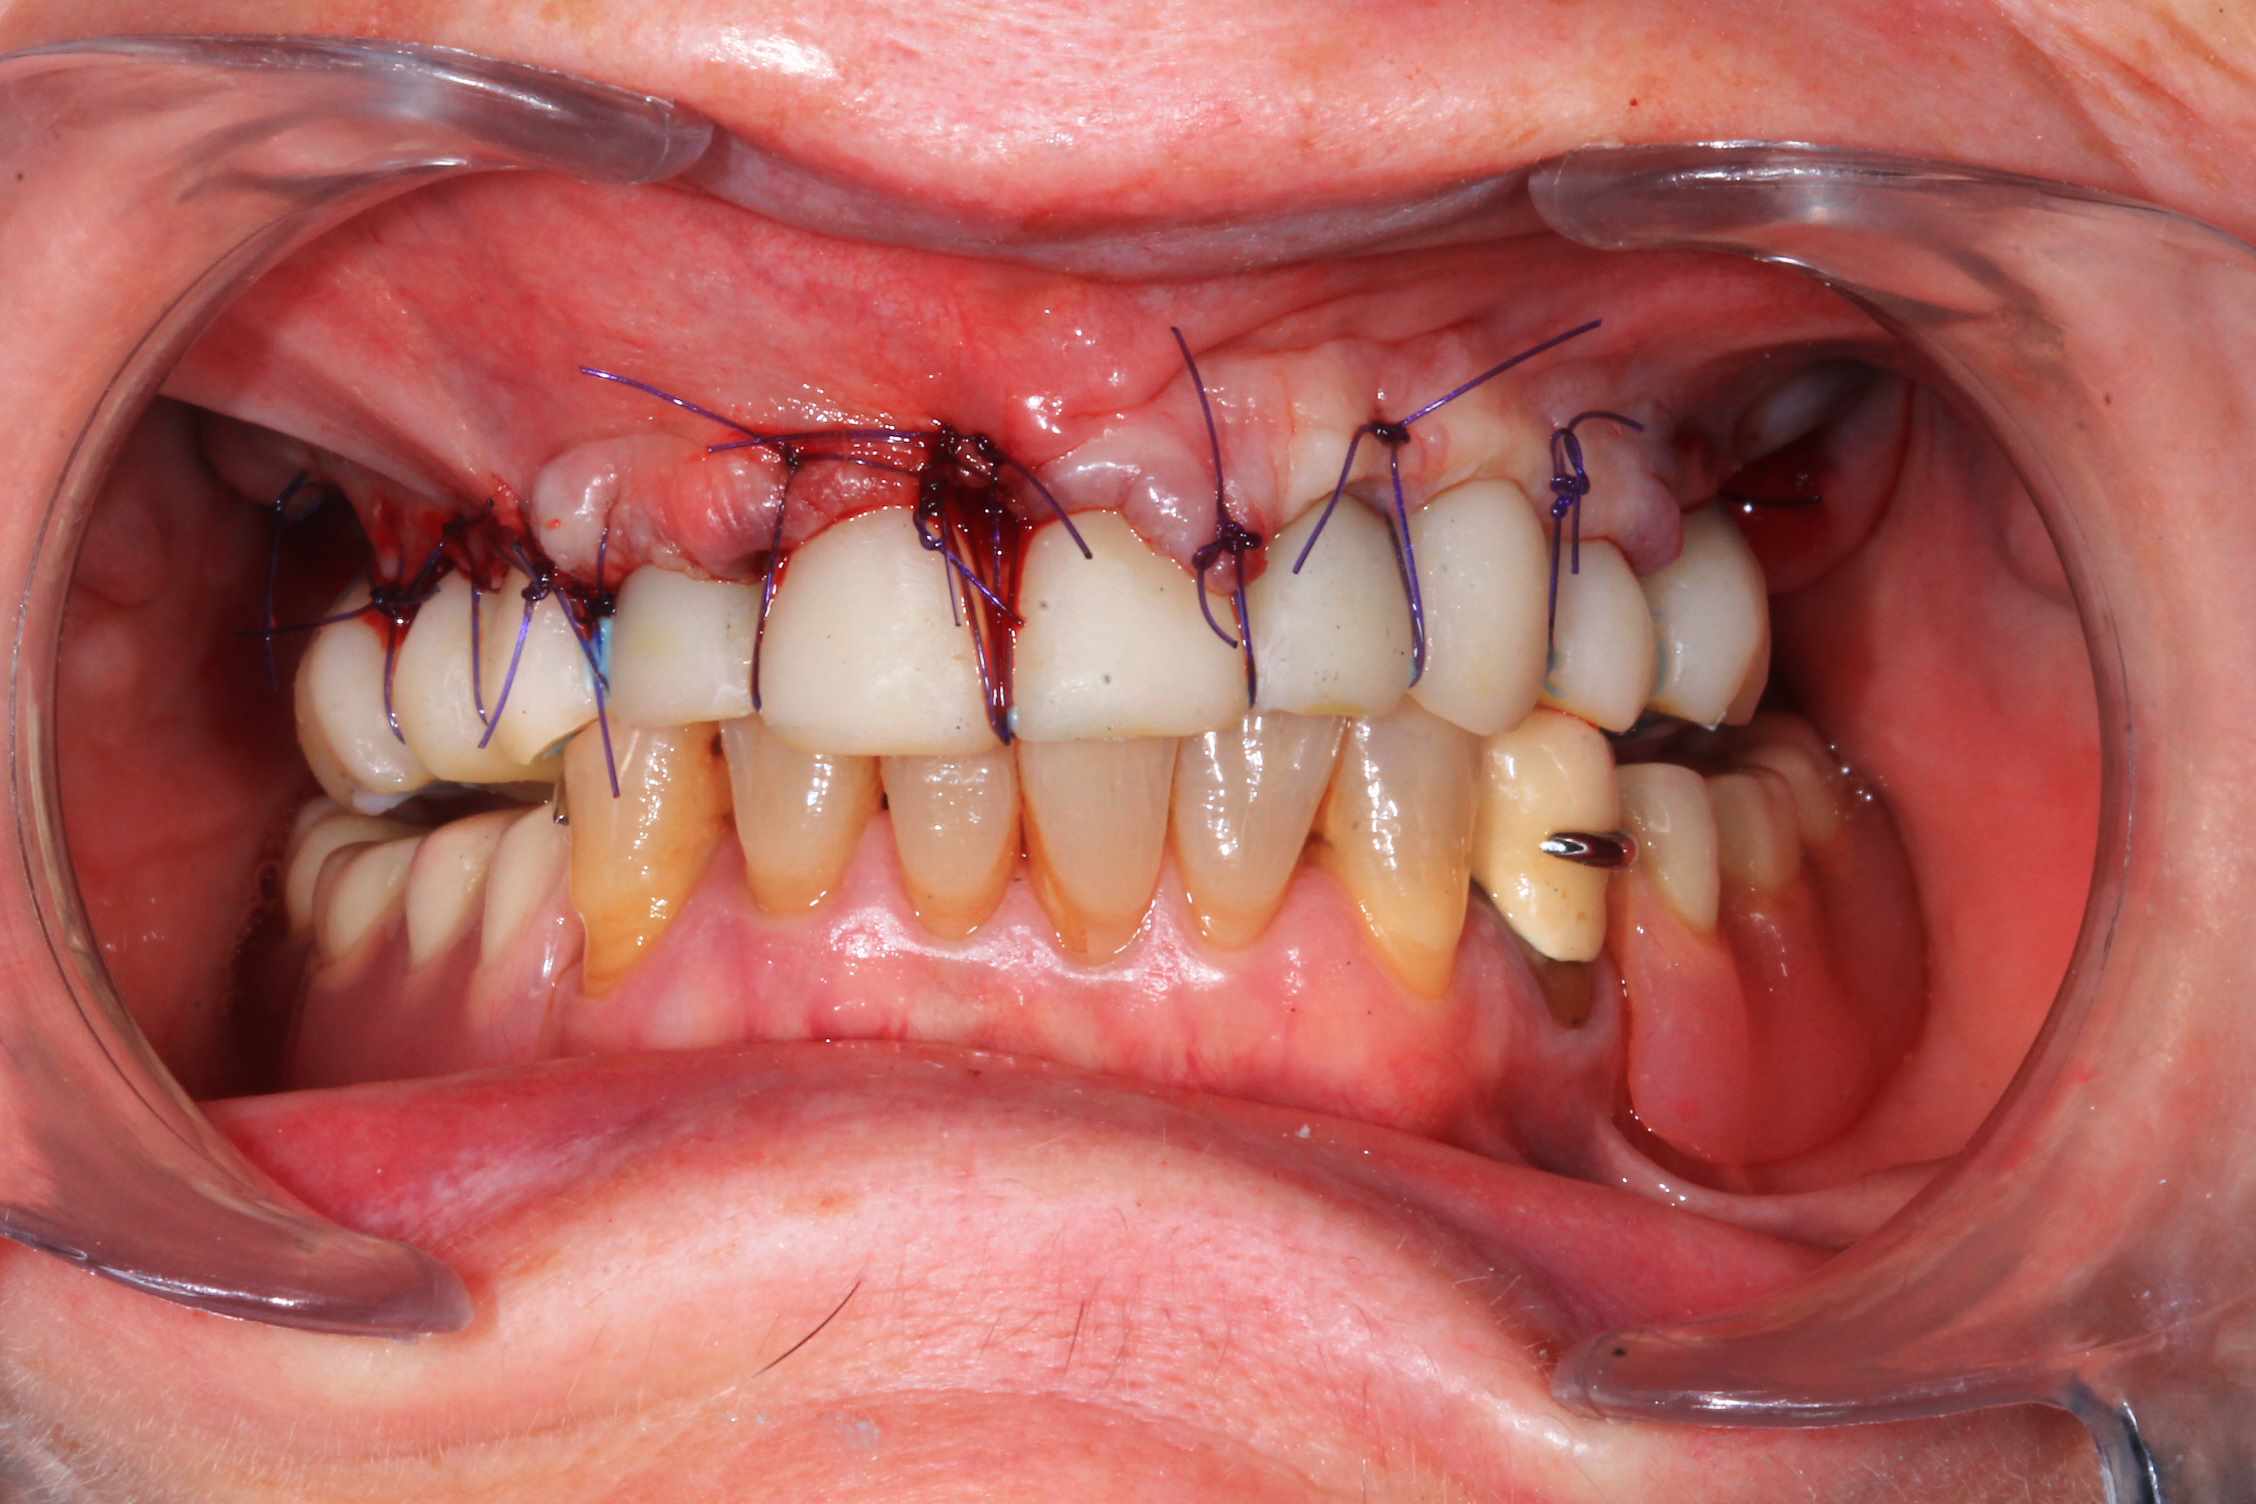

Guide métal avec support clavette, os assez fin : il est prévu un sticky bone complet : donc : lambeau avant extraction, positionnement du guide base et forage des clavettes, positionnement du guide implant, pose des piliers MU, controle des axes prothétique avec le guide pilier, collage des piliers prov sur le bridge a armature métal, occlusion nickel, sticky bone et PRF, sutures suspendues.

Ce qui ne vas pas : les dents un peu trop courte sur le provisoires, et le plan d'occlusion. L'erreur est de ne pas avoir utilisé Cadsmile3d pour le smile design du provisoire.

Voilà les photos du cas , avec un peu de retard.

06C757A0-0679-4A5E-A2AD-9E867A3CB080.jpeg

65672A94-F454-46C1-A2A7-47927485B543.jpeg

143DCC8C-EA6F-4EE5-9915-F12A33C377B9.jpeg

F8362BF2-81BC-455C-BFD0-A9FE9451F3F4.jpeg

91CE34AF-EDB6-436D-8B12-726F81FC0CB1.jpeg

4060EC60-1F78-4778-B0E3-5FE470671FDF.jpeg

F4ECCBAA-30DE-407C-AAD1-02D226210CC9.jpeg

C4C89A41-3628-4190-A864-AFFC591089BF.jpeg